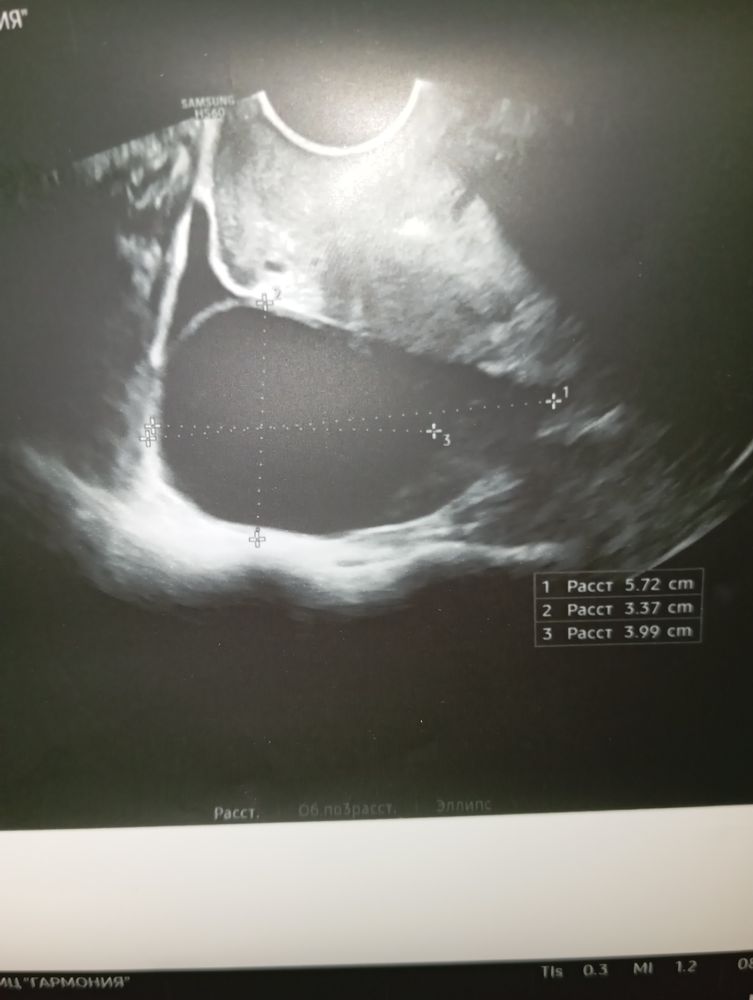

На 19 дц переделала в другом месте: киста жт 5х4см справа, энд 12мм (погрешность измерений?).

Фото 2: УЗИ 19 дц